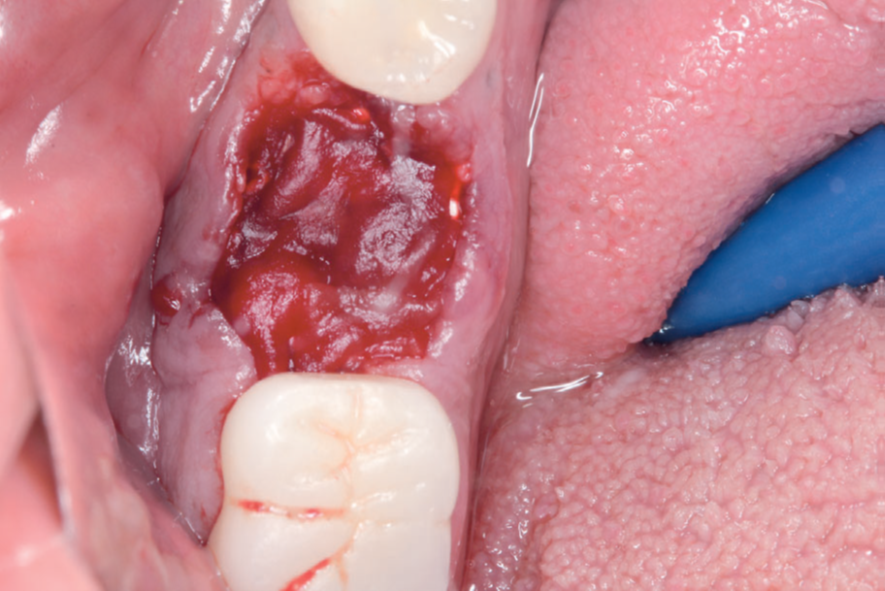

Para a regeneração óssea guiada, o substituto ósseo natural composto por hidroxiapatita bovina e colágeno do tipo I (Extra Graft XG-13) foi introduzido ao redor do implante para preenchimento do GAP (Figura 7). Depois, uma barreira regenerativa não absorvível (Cytoplast) foi recortada, adaptada e colocada, seguida por uma membrana biológica bovina (Figuras 8 e 9). O procedimento cirúrgico foi finalizado com a realização da sutura com fio de nylon 5.0. Para verificar o posicionamento do implante dentário, uma radiografia periapical foi realizada imediatamente à cirurgia (Figura 10).

Neste relato de caso, a remoção da membrana Cytoplast foi feita aos 15 dias do pós-operatório. Depois de 23 dias, foi realizado o acompanhamento da cicatrização local (Figuras 11 e 12). Seis meses depois, a paciente voltou para realizar a reabertura da área cirúrgica (Figura 13) e retirada do parafuso de cobertura, visando à fase da reabilitação protética. Após a reabertura e remoção do parafuso de cobertura (Figura 14), e uso do Túnel Check para prótese cone-morse (estojo protético Implacil De Bortoli), foi selecionado o cicatrizador com dimensões de 4,5 mm x 5,5 mm (Figura 15) para guiar o condicionamento gengival (Figura 16). A reabilitação protética ainda está em andamento para finalização do caso (Figura 17).